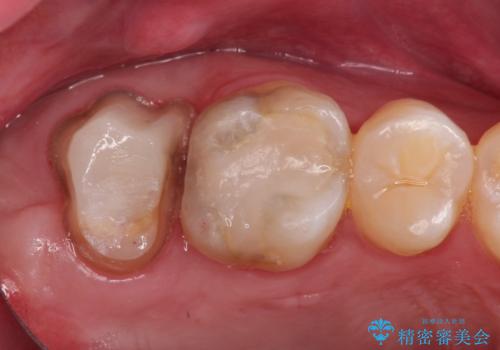

- 治療計画

- 患者様は、右側の奥歯でしっかり噛めないことを主訴に来院されました。診察の結果、右上6・右下6の根管治療が不十分で、感染のリスクがある状態と判断。これらの歯は再根管治療を行い、セラミッククラウンで補綴することにしました。また、右上7・右下7は欠損しており、噛み合わせを回復するためにインプラント治療を計画しました。

まず、右上6・右下6の根管治療を再度行い、根の状態をしっかり整えた上で、セラミッククラウンを装着しました。さらに、欠損していた右上7・右下7にはインプラントを埋入し、セラミッククラウンを装着。治療後は、「奥歯でしっかり噛めるようになり、不安なく食事ができるようになった」と患者様にも大変ご満足いただきました。